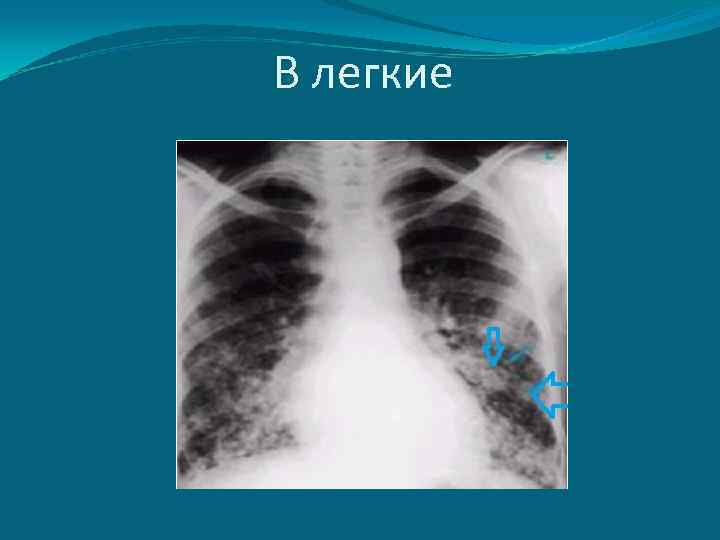

Гематогенное метастазирование гематогенное метастазирование: легкие - от 4, 4 до 14% случаев, кости - от 1 до 8% наблюдений печень, головной мозг (более редко, в основном при недифферецированных формах заболевания ) (Пачес А. И. , Пропп Р. 2008 )

В легкие